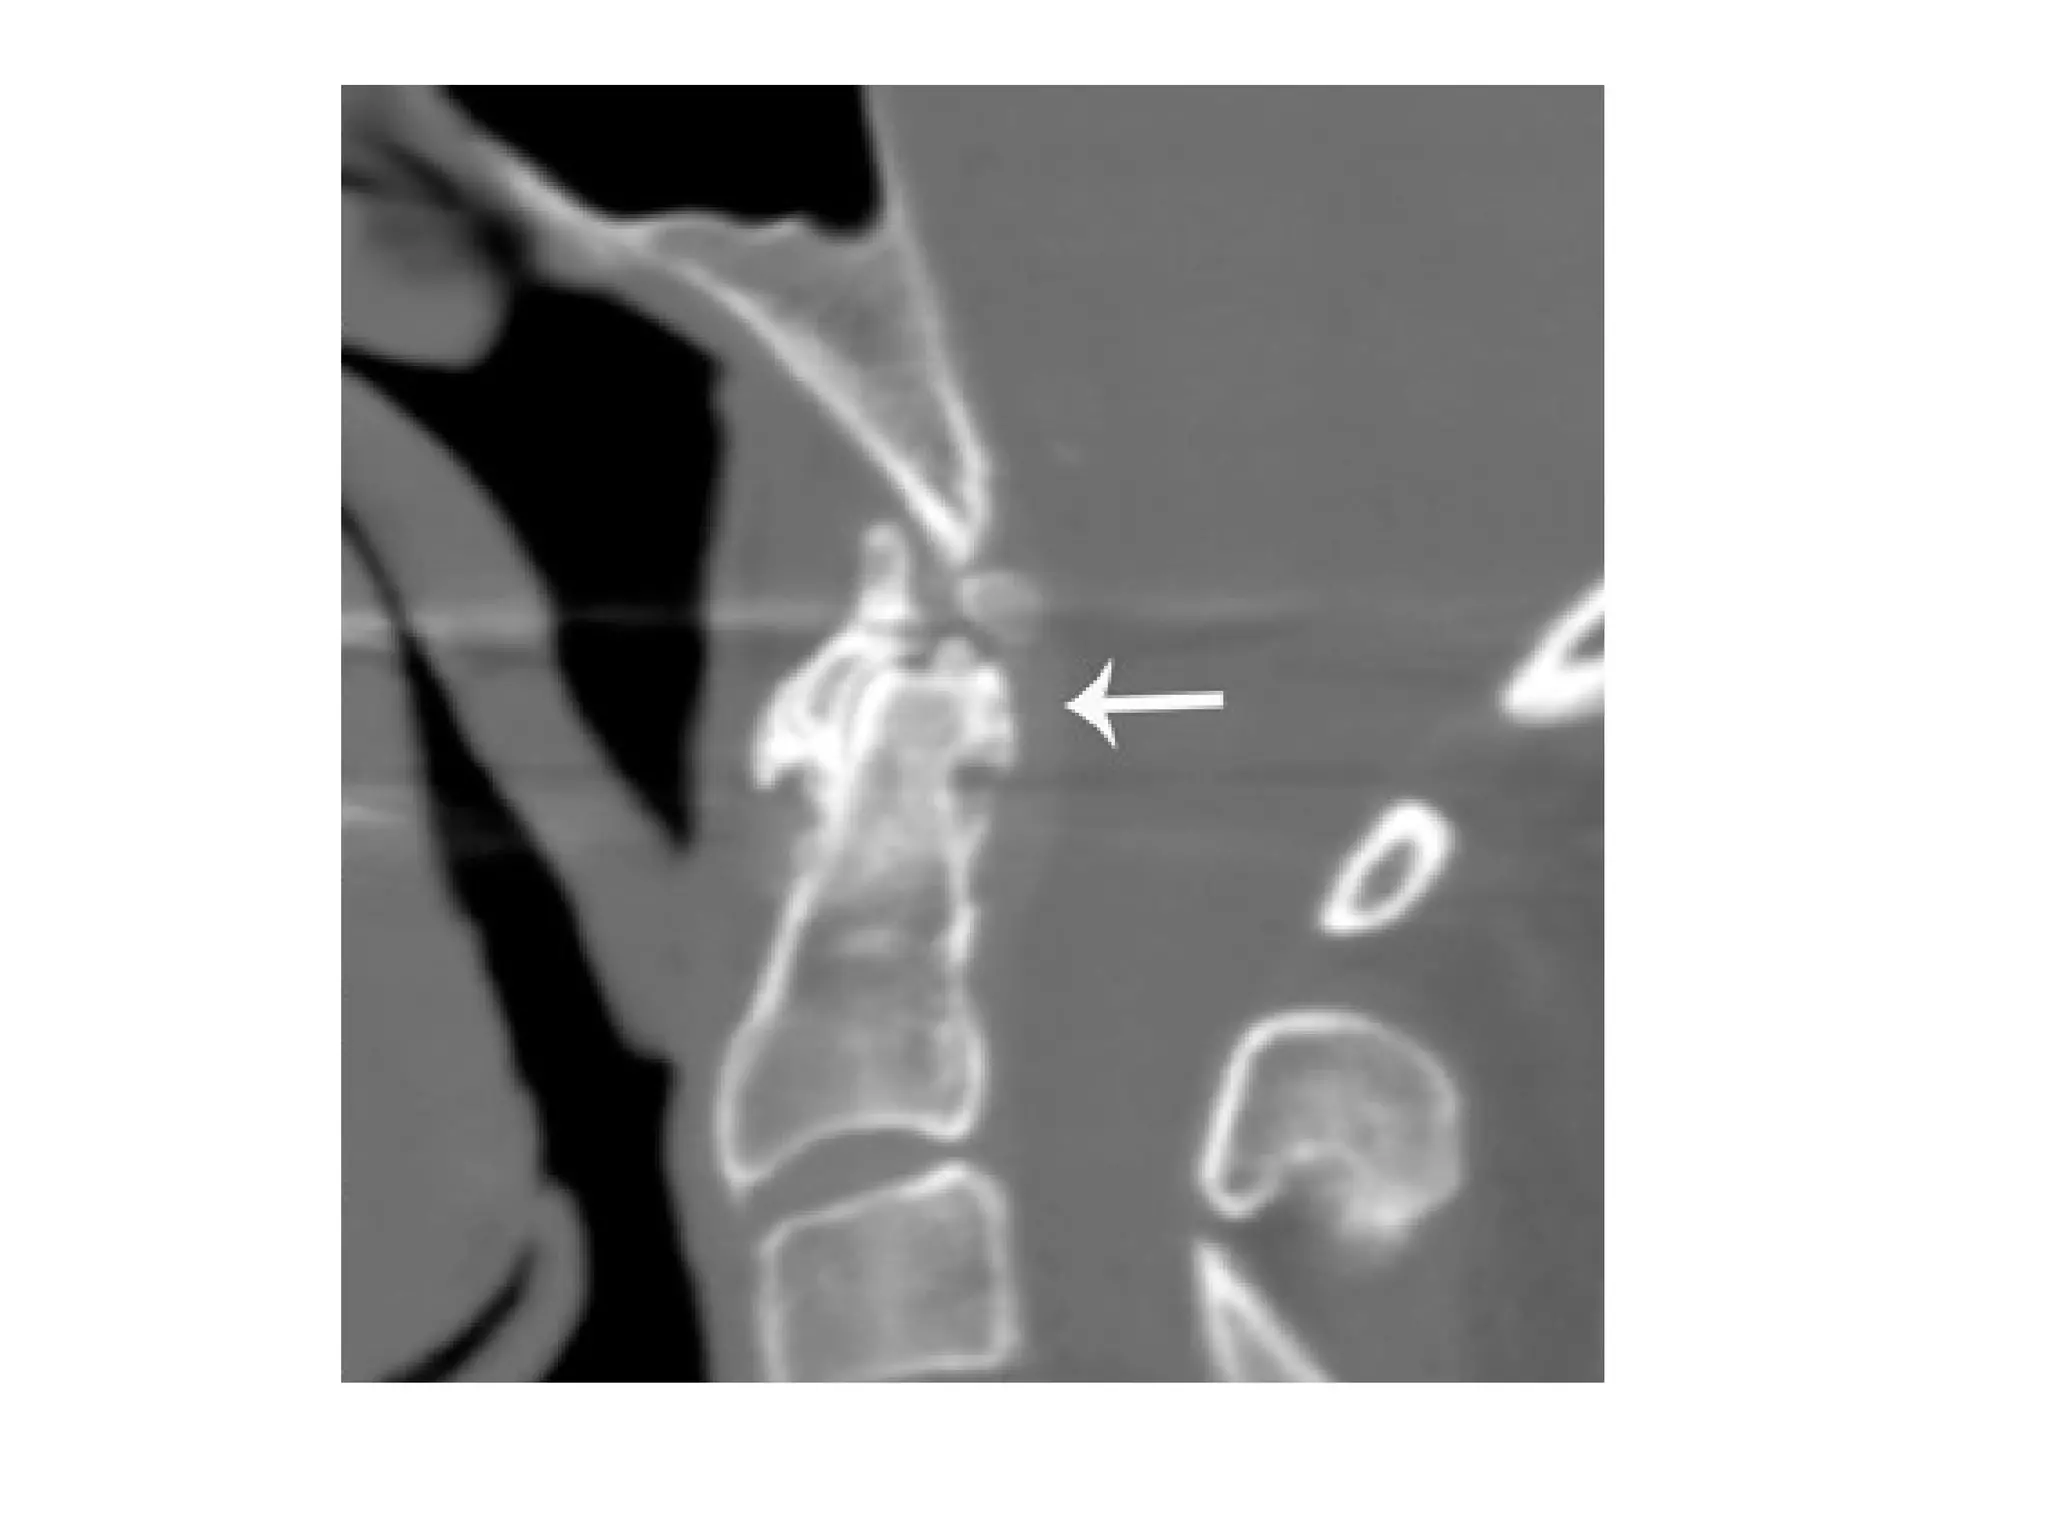

CT cervical spine lateral view Partially calcified pseudomass behind the dens , extensive narrowing

and erosive changes of the end-plates at the C2-C3 level , large erosion anteriorly in the C3 body

, intervertebral disc calcifications at the C6-C7 and C7-Th1 levels , calcifications in the posterior

and anterior longitudinal ligaments and annulus fibrosus , calcifications at the interspinous

ligament C7 , spondylophyte formation anteriorly